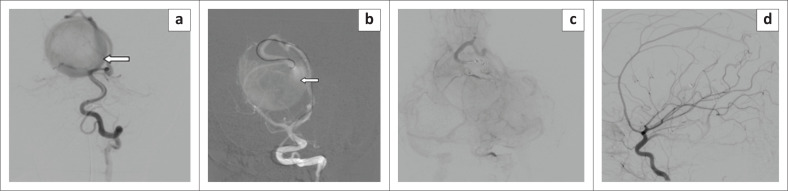

盖伦静脉动脉瘤畸形(VGAM)是一种罕见的先天性畸形,其特征是原始脉络膜动脉和正中前脑静脉(盖伦静脉的胚胎前体)之间的动静脉瘘。血管内技术改变了这些患者的治疗方法,改善了预后。一名八个月大的 VGAM 患者在使用乙烯-乙烯醇共聚物(EVOH)进行血管内栓塞治疗后,出现了罕见的并发症--化学脓肿。经保守治疗后,临床效果良好:贡献:EVOH栓塞术后的化学脓肿很少见,影像学鉴别包括脑脓肿和玛瑙肉芽肿。了解并成功识别这一实体至关重要,因为其治疗和预后各不相同。化学脓肿可采取保守治疗,预后良好。

Vein of Galen aneurysmal malformation (VGAM) is a rare congenital malformation characterised by arteriovenous fistulas between primitive choroidal arteries and the median prosencephalic vein, the embryonic precursor to the vein of Galen. Endovascular techniques have changed the management of these patients with improved prognosis. An eight-month-old with VGAM managed by endovascular embolisation using ethylene vinyl alcohol copolymer (EVOH) developed a chemical abscess - a rare complication. It was managed conservatively and showed promising clinical outcome.

Contribution: Chemical abscesses following EVOH embolisation are scarce - with imaging differentials, which include brain abscess and onyx granuloma. Knowledge and successful identification of this entity are essential as its management as prognoses differ. Chemical abscess is managed conservatively and has a good prognosis.